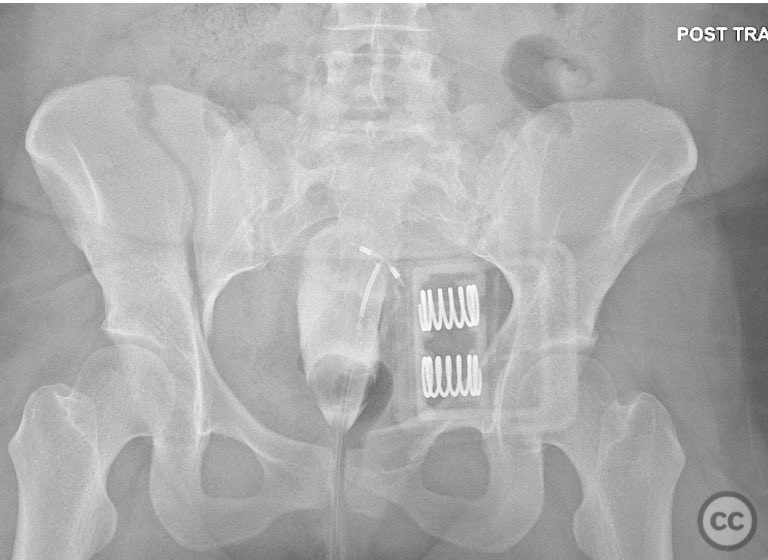

Clinical Details

Clinical and radiological findings:  A 26-year-old female sustained a closed pelvic ring injury following a motor vehicle accident. She was hemodynamically stable, neurologically intact, and had no other associated injuries. Skin integrity was preserved. Initial management included pelvic binder application and 10 pounds of distal femoral skeletal traction. Portable AP pelvic radiograph demonstrated a left-sided sacral fracture with associated ipsilateral iliac wing and pubic ramus fractures, consistent with an AO/OTA 61-B2 (lateral compression type II) injury pattern.

Orthopaedic implants used:   Two 7mm diameter cannulated fully threaded medullary screws (iliac crest and pelvic brim), percutaneous iliosacral screw(s).